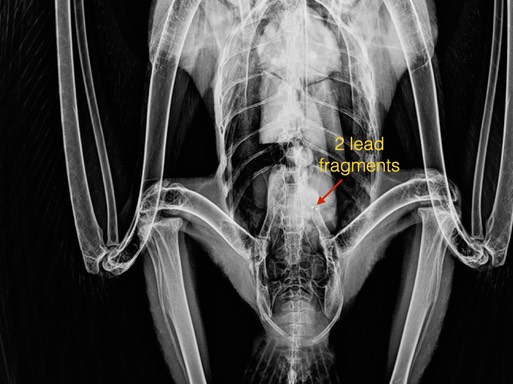

Bald Eagle 22-424

We could not save a Bald Eagle that came from Enterprise, Oregon this past week. He died of lead poisoning. Raptors, and other wildlife who scavenge, are secondarily poisoned when they feed on gut piles or carcasses of animals that have been shot with lead ammunition.

The x-ray below shows two small pieces of lead in the eagles gut. The eagle’s blood tested ”high” which means the lead was above 66 micrograms/deciliter. Ten micrograms per deciliter is considered a toxic level of lead. We know lead is toxic and there is no safe level of lead in our food. I understand there are significant costs in switching from lead to nonlead ammunition, but the cost of not switching is even higher. For information about nonlead alternatives visit Hunting with Nonlead.